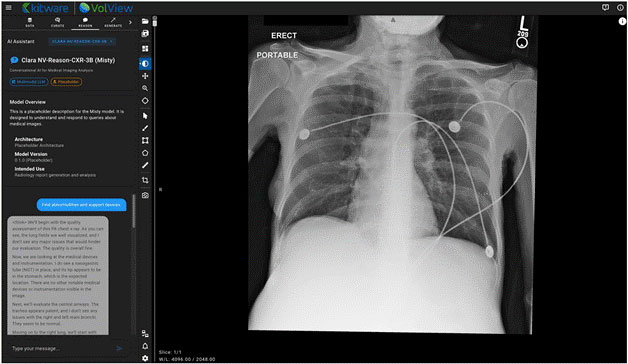

NV-Reason-CXR-3B — Clinically Aligned Chain-of-Thought Reasoning

NV-Reason powers an interactive, multimodal chat interface inside VolView, allowing users to ask questions directly about an image and receive structured, interpretable reasoning. This creates opportunities for explainability, teaching, quality assurance, and exploratory research.

During the demo, we show whole-body organ segmentation overlays, interactive correction, multimodal reasoning on chest X-rays, and the generation of high-fidelity synthetic CT volumes. The session concludes with deployment guidance and a Q&A session on customization, cloud scale-out, and governance.